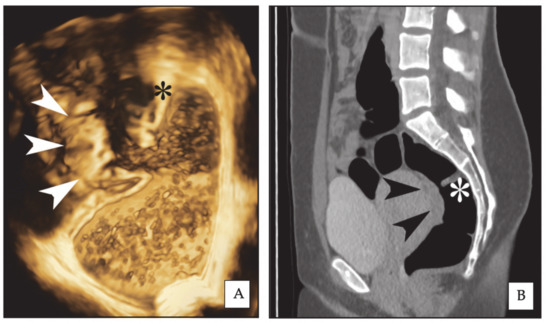

2.1. Three-Dimensional Rectal Water Contrast Transvaginal Sonography

2.2. Computed Colonography